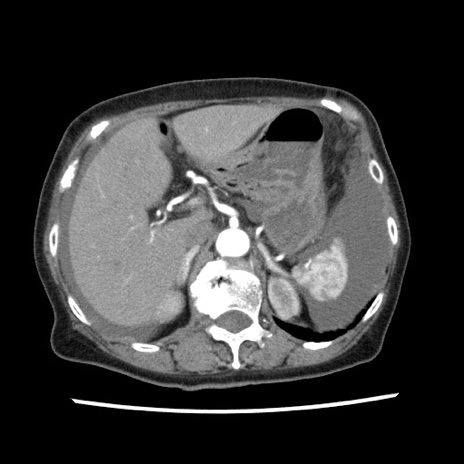

矢状断像